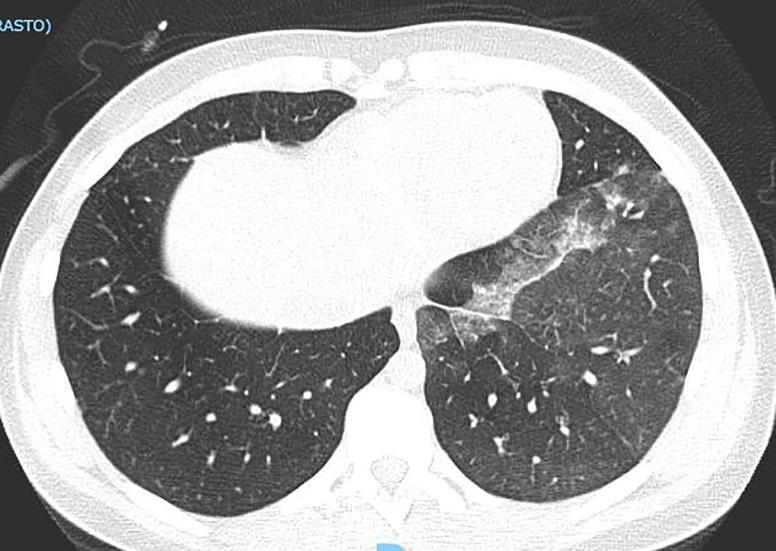

Acute Pediatric COVID-19: CT

21 Imaging of Covid 19 infection in children

3 Phases

Early: "Halo" sign

Local infection

Progressive: Diffuse GGO

Developed: Consolidation

Surr vasc congestion

Inflammation - adj alveoli

Alveoli fill with fluid/cells

COVID 19

• Patchy bilateral GGO, Consolidations or both

• Bilateral & multifocal GGO, +/Consolidations or both

• Halo sign (Early)

• Peripheral and lower lung zone predominance